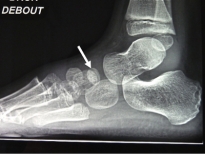

Exemple d'ostéochondrite de l'os scaphoïde (naviculaire) chez un garçon de 5 ans:

Les deux photos de gauche montrent un os densifié et aplati sur le pied gauche.

Les deux photos de droite montrent les mêmes radios sur le pied droit sain.